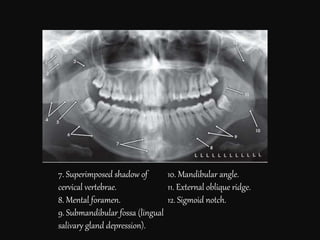

7. Superimposed shadow of

cervical vertebrae.

8. Mental foramen.

9. Submandibular fossa (lingual

salivary gland depression).

10. Mandibular angle.

11. External oblique ridge.

12. Sigmoid notch.